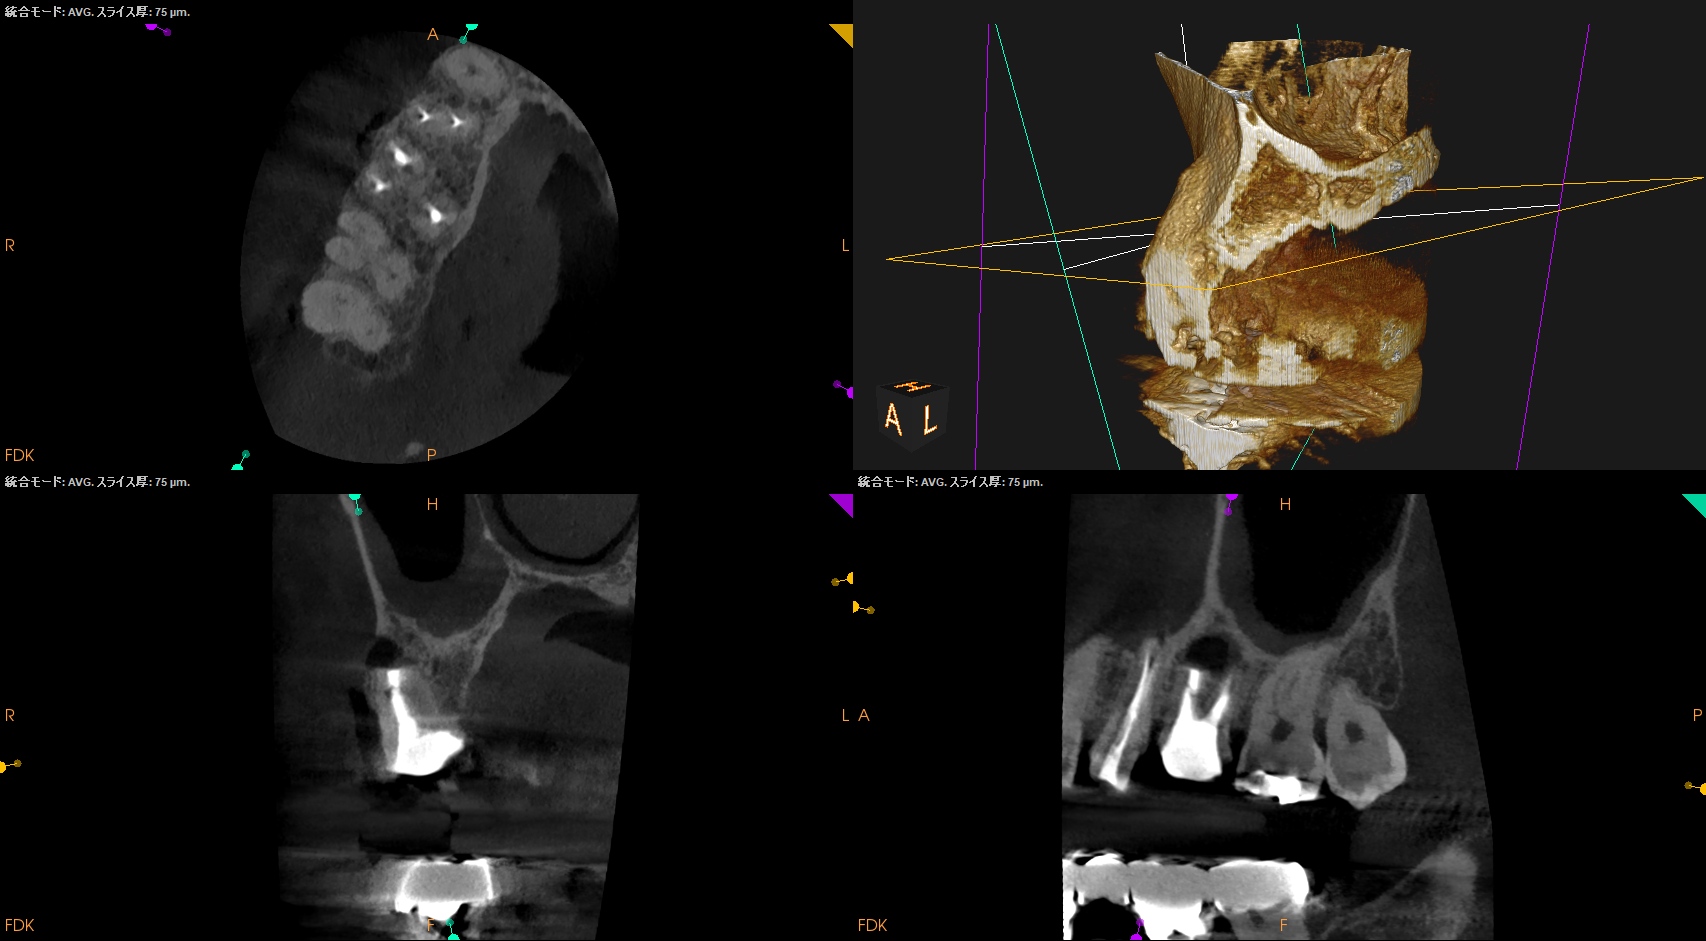

治療前の予測としては以下だ。

CEJよりも13mm先にApexがある。

が、この際にOsteotomyを行わなくてもApexには辿り着ける。

そしてApexから3mmで切断した時に、頬舌的には4.4mm削るだけで済む。

Very easyな外科治療だ。

そしてその際、Gutta PerchaがMBの中心にあることからこの根管は1根管であるということまでわかる。

まさにSuper easyなApicoectomyである。

このように

見れる・わかる・映りがいいCarestream社のようなCBCTがあれば, ここまで術前に予測ができるのである。

それは砂漠を旅する際にMapを手に入れることができうようなものである。